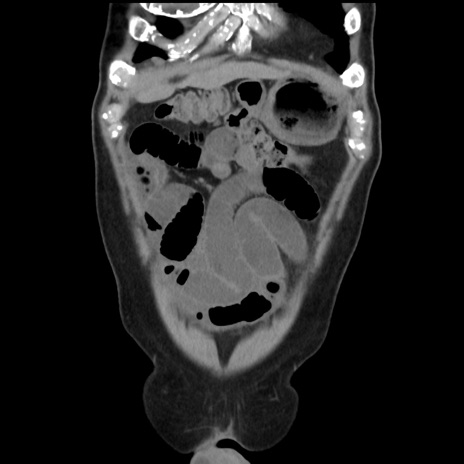

症例16(冠状断像)

【症例】 70歳代男性

【主訴】 腹痛、嘔吐

【現病歴】 約1ヶ月前より間欠的に腹痛と嘔吐あり、当院消化器内科を受診したところCTで多発する肝臓のLDAを指摘され、精査中であった。以降は消化器症状は安定していたが、2日前より嘔気と腹痛があり、同日より排便・排ガスが消失した。改善認めず、 本日、救急外来を受診した。

【身体所見】意識清明・会話良好、BT 36.3℃、BP 127/80mmHg、 P 80bpm、腹部:膨満あり、平坦・軟、上腹部正中および下腹部正中に圧痛あり、反跳痛なし、筋性防御なし。

【データ】WBC 7200、CRP 0.77